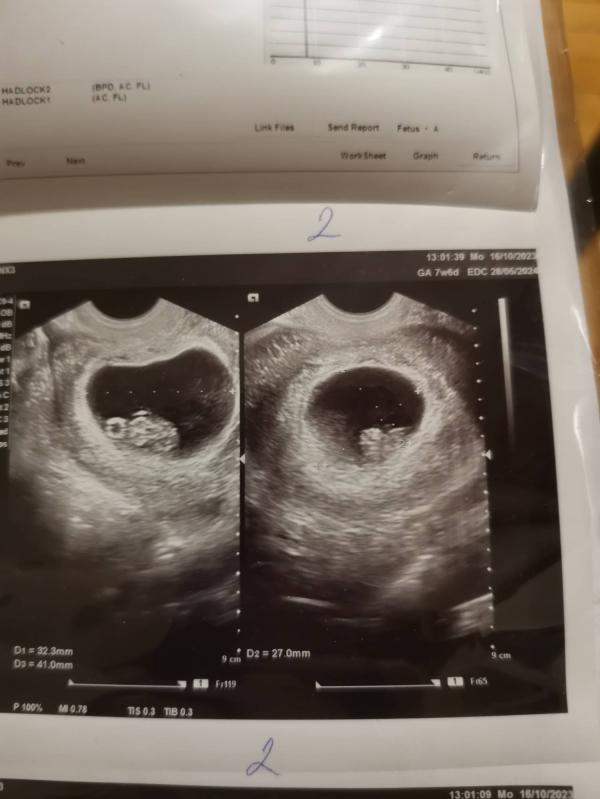

А вот и малыши))

Первый чилит в дне матки. 17 мм ростом, желточный мешочек 6 мм, ЧСС 175 уд/мин.

Второй - под ним, по задней стенке справа. Рост 16,8 мм (догнал первого), желточный мешочек 5 мм, ЧСС 189 уд/мин.

Оба опережают развитие на 2 дня.

Слава Богу, гематома рассосалась!